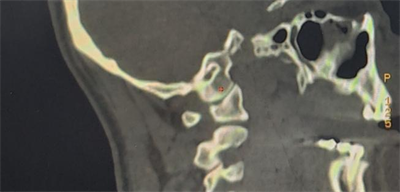

面对手术的高难度、高风险,更是考虑到患者辗转多处求医的难处,颈椎治疗经验丰富的外科团队知难而上、敢于亮剑,讨论制定了周密的手术方案,决定在CT实时监测引导下,实施颈椎后入路寰枢椎椎弓根螺钉固定复位、植骨融合术,使手术操作更可视化、精准化,降低手术风险。

经过充分的准备和反复演练,由科主任国华,副主任医师杨兆平、高胜一组成的外科团队与放射、麻醉团队密切配合,先取出患者自体髂骨用于植骨,随后利用CT扫描获得患者实时影像数据,避开椎动脉和脊髓,将螺钉准确植入寰枢椎椎弓根,经过近三个小时的手术,成功将患者寰枢椎牢固固定并植骨。

CT实时监测